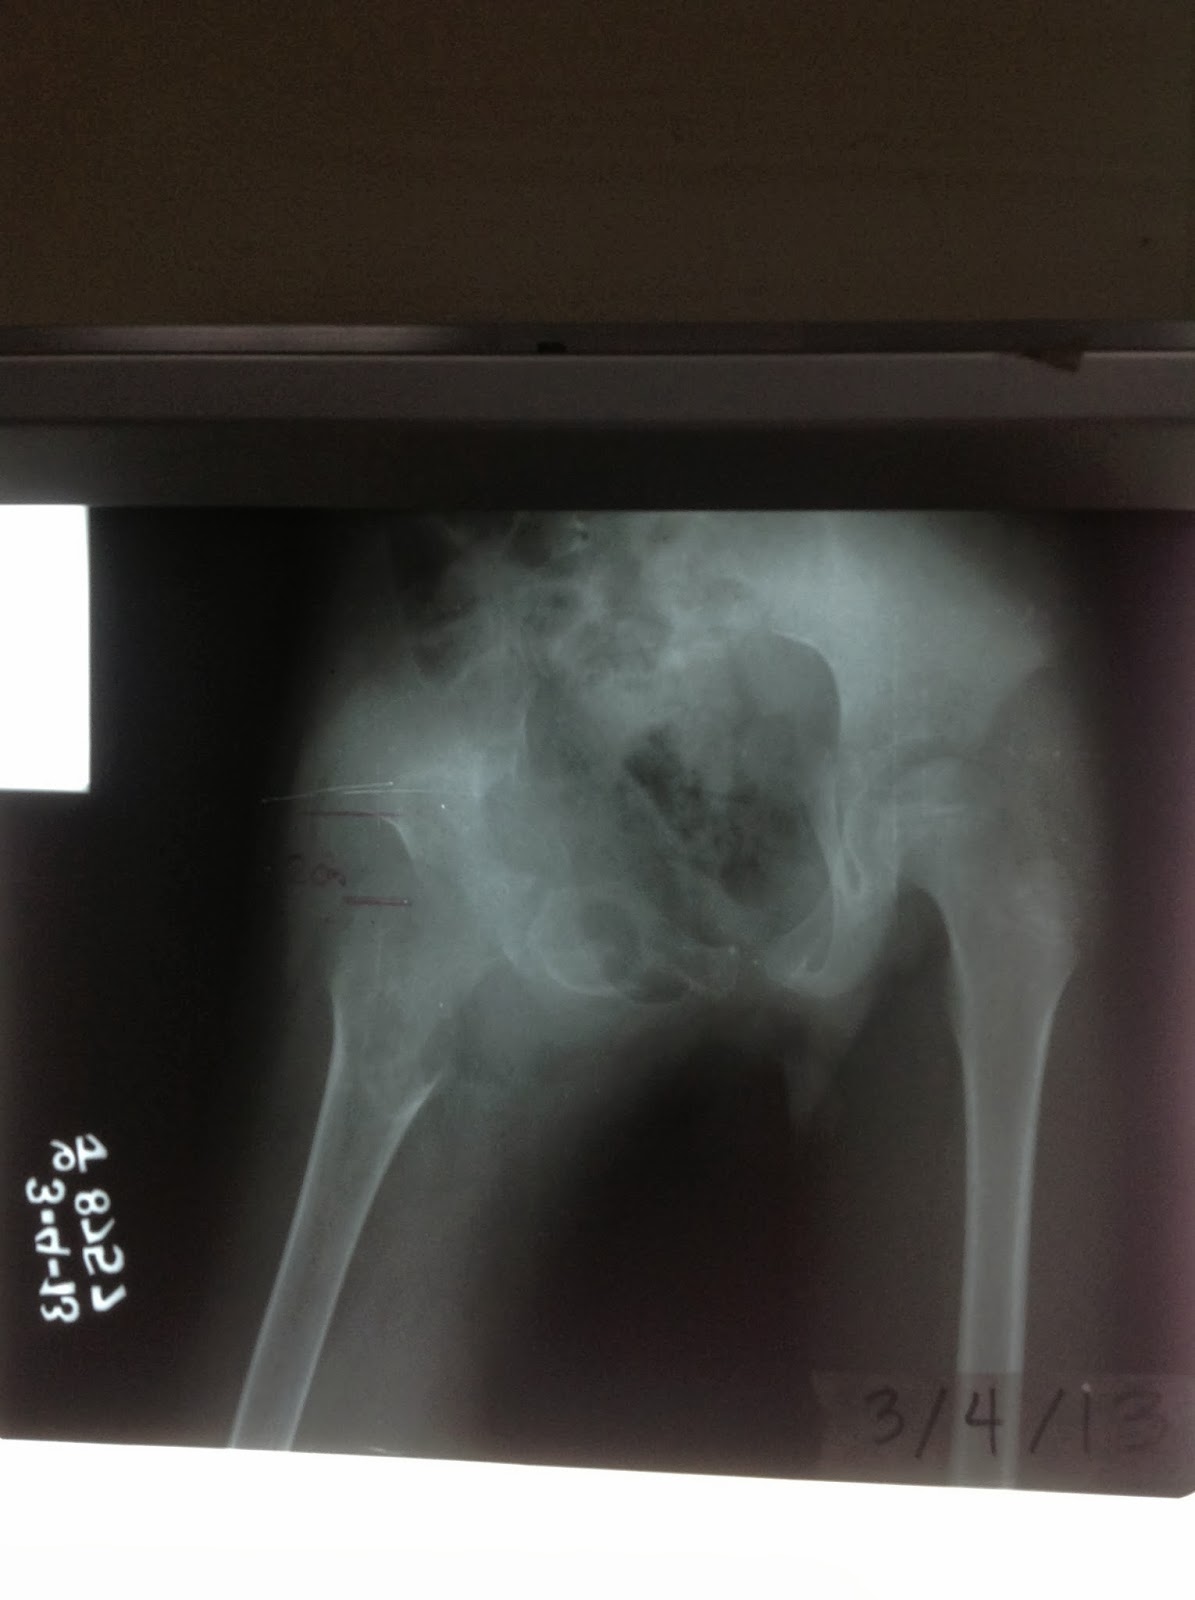

sunburst appearance

sunburst appearance associated with osteosarcoma

femoral head displaced